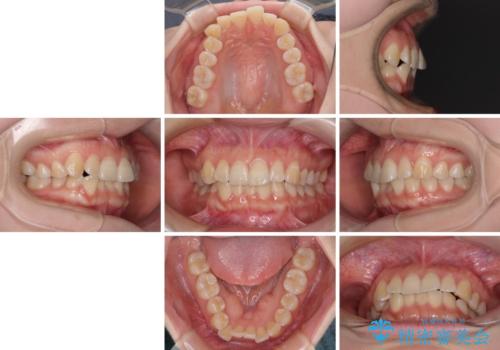

- 上下前歯のデコボコを気にして来院された患者様です。

ワイヤー矯正でもインビザライン矯正でも対応可能でしたが、インビザラインでの自己管理の煩わしさを避けるため、ワイヤー装置にて矯正治療を行うこととしました。

患者様も驚く、僅か10か月での治療終了となりました。

下顎前歯が1歯欠損しているため、上下正中は合わず、左右奥歯の咬み合わせは理想的とはならない仕上がりとなります。